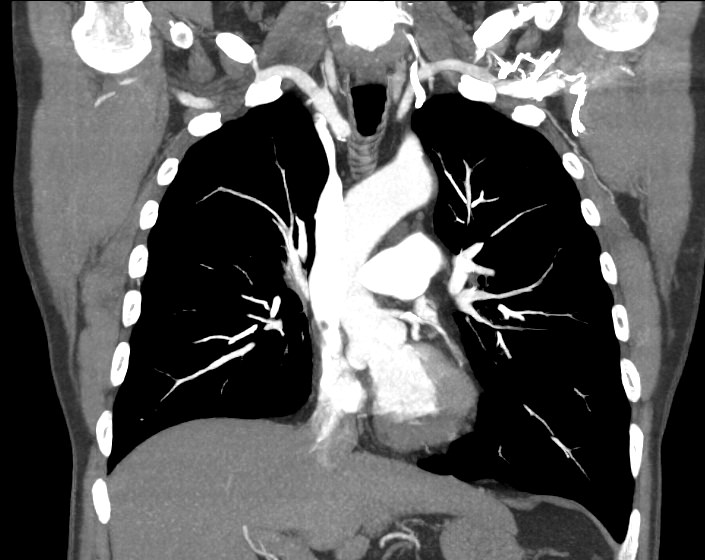

Компьютерная томография позволяет детально визуализировать структуру лимфатических узлов, выявить ее неоднородность, гиперплазию, определить деформацию контуров, появление инфильтрации окружающих тканей с образованием пакетов и конгломератов лимфоузлов.

В нашей клинике обследование лимфоузлов брюшной полости и забрюшинного пространства выполняется на современном мультиспиральном томографе экспертного класса TOSHIBA AQUILION CXL, который при помощи рентгеновских лучей производит послойное сканирование исследуемой области. Аппарат оснащен 128 высокочувствительными детекторами, расположенными по спирали, что позволяет за короткое время выполнять сканирование нескольких областей тела. Это значительно сокращает время исследования и снижает уровень лучевой нагрузки на пациента.

Полученные данные посредством инновационных цифровых приложений преобразуются в трехмерные изображения высочайшего качества, что позволяет проводить точную и достоверную диагностику.

С целью повышения контрастности изображений, выявления патологических изменений в лимфоузлах дополнительно внутривенно вводится рентгеноконтрастное вещество на основе йода. Контраст накапливается в патологических очагах и под воздействием рентгеновских лучей обусловливает их яркое изображение на фоне неизмененной ткани. Контрастирование значительно повышает диагностическую ценность исследования и помогает выявлять многие серьезные заболевания на начальных этапах.